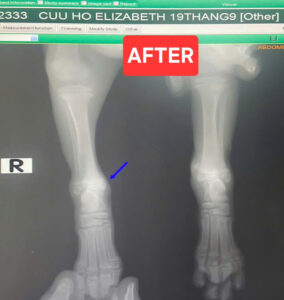

X ray. Replace the bone back to joint. Cast. Treated the infection and inflamation. Strictly care for 21 days.

Out come: CAN RUN LIKE CRAZY NOW. 😀🥰